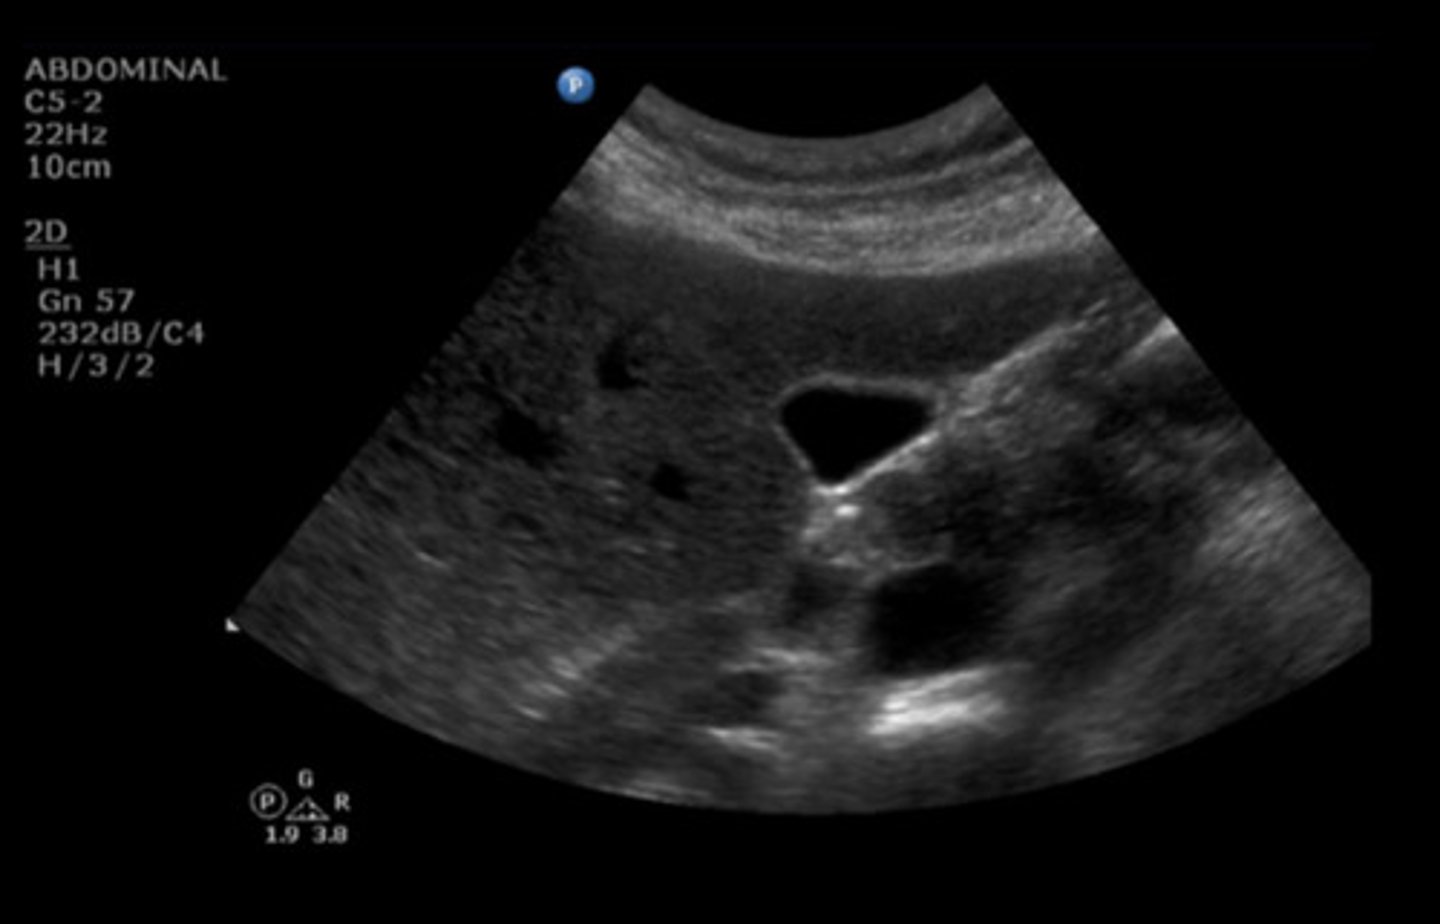

CBD

Identify the following;